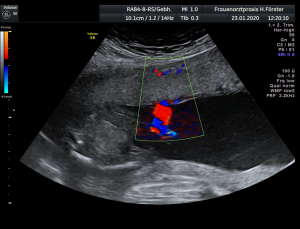

Gynäkologische Grundversorgung Frauenärztliche Krebsfrüherkennungsuntersuchung Nachsorge und supportive Therapie bei bösartigen gynäkologischen Tumoren Impfungen Brustultraschall Ultraschalluntersuchung der weiblichen Genitalorgane Psychosomatische Grundversorgung Chlamydienscreening FOB-Test (früher Hämoccult) Kontrazeption Geburtshilfliche Grundversorgung Geburtshilflicher Basisultraschall Erweiterter Basisultraschall (Organscreening) zw, 18-22.SSW Doppler/Duplexsonografie des fetomaternalen Gefäßsystems Infektionsscreening in der Schwangerschaft CTG (Kardiotokographie) Gynäkologische Grundversorgung Dies umfasst die Abklärung und Behandlung gynäkologischer Erkrankungen. Eine große Rolle dabei spielt das ärztliche Gespräch, ergänzt bei Notwendigkeit durch die gynäkologische Untersuchung oder Untersuchung der weiblichen Brust. In vielen Fällen werden noch Zusatzuntersuchungen durchgeführt (z.B. Ultraschalluntersuchungen, Abstrichentnahmen, Blutentnahmen) oder weiterführende Untersuchungen veranlasst (z.B. Röntgenuntersuchungen). >> zurück << Frauenärztliche Krebsfrüherkennungsuntersuchung Die Krebsfrüherkennungsuntersuchung der Frau ist wahrscheinlich die bekannteste Leistung unseres Fachgebietes. Ab dem Alter von 20Jahren hat jede Frau ein Anrecht auf diese jährliche Untersuchung. Dabei werden der Unterleib der Frau und ab dem Alter von 30Jahren auch die Brüste der Frau systematisch klinisch untersucht. Zusätzlich erfolgte seit vielen Jahren ein Pap-Abstrich vom Gebärmutterhals. So konnten Zellveränderungen meist rechtzeitig erkannt und behandelt werden und es wurde erreicht, daß das früher sehr häufige Zervixkarzinom (Gebärmutterhalskrebs) heute nur noch selten auftritt. Um die Qualität weiter zu verbessern erfolgte 2020 eine Neuordnung des Screenings mit Überarbeitung der Abstrichintervalle und Hinzunahme von HPV-Abstrichen ab 35 als Kassenleistung. >> zurück << Nachsorge und supportive Therapie bei bösartigen gynäkologischen Tumoren Nach Abschluss und oft auch wärend der Primärbehandlung können Probleme auftreten. Es macht also Sinn, sich in regelmäßigen Abständen zu treffen, um das weitere Vorgehen zu planen, eventuell Zusatzuntersuchungen zu veranlassen oder zusätzlich wegen der Beschwerden zu behandeln. Die Nachsorgeuntersuchungen finden anfangs engmaschig statt, später werden die Intervalle länger. >> zurück << Impfungen In Zeiten der Globalisierung, zunehmender Reisefreudigkeit und Zuwanderung werden wir wieder mit Infektionserregern konfrontiert, die wir schon als besiegt geglaubt hatten. Gleichzeitig werden wir immer älter und unser Immunsystem dabei nicht besser. Es reicht nicht, mal eben alle 10Jahre Tetanus zu impfen. Sind Sie geschützt? Wissen Sie was empfohlen ist? Bringen Sie den Impfausweis (auch den alten!!) mit. Wir prüfen Ihren Impfstatus, geben Ihnen Empfehlungen. Die gängigsten Impfstoffe haben wir auch vorrätig und können Sie impfen. >> zurück << Brustultraschall Die Ultraschalluntersuchung der Brust (Mammasonografie) kommt zur Abklärung von krankhaften Veränderungen zur Anwendung oder als Zusatzuntersuchung in der Früherkennung von Brustkrebs bei sehr dichtem Gewebe oder familiärer Vorbelastung. Sie ersetzt nicht das organisierte Mammographiescreening und ist nicht Bestandteil der normalen Krebsfrüherkennung. Es handelt sich um eine schmerzfreie Untersuchung ohne Strahlenbelastung. Die Mammasonografie  ist auch als Wunschleistung (IGeL) möglich. >> zurück << Ultraschalluntersuchung der weiblichen Genitalorgane Die Ultraschalluntersuchung der weiblichen Genitalorgane kommt zur Abklärung von krankhaften Veränderungen des weiblichen Genitales zur Anwendung. Dabei werden mit einer hochfrequenten Vaginalsonde die Organstrukturen im kleinen Becken untersucht. Die Untersuchung ist bei schlanken und sehr jungen Frauen auch vom Bauch aus möglich, die Genauigkeit ist dabei technisch bedingt aber schlechter.  Sie ist nicht Bestandteil der normalen Krebsfrüherkennung. Auch diese Untersuchung ist als Wunschleistung (IGeL) möglich. >> zurück << Psychosomatische Grundversorgung Jede Erkrankung belastet die Seele. Eine seelische Belastung macht den Körper krank. Jeder weiß das. Die Zusammenhänge zwischen dem kranken Körper und der kranken Seele beschreibt die Psychosomatik. Ein "Gordischer Knoten", der nur schwer zu zerschlagen ist, oft ein langer Weg. Ziel ist es, diese Zusammenhänge zu erkennen und den Betroffenen zu helfen ihren Weg zu finden. Oft ist die Zusammenarbeit mit einer Psychologin/ Psychologen nötig. Wichtig ist die Hilfe bei den ersten Schritten. Laufen müssen Sie selbst. >> zurück << Chlamydienscreening Das Bakterium Chlamydia trachomatis kann beim Sex übertragen werden und zu Entzündungen und sogar zur Unfruchtbarkeit führen. Deshalb bezahlen die Krankenkassen bis zum vollendeten 25.Lebensjahr allen sexuell aktiven Frauen einen Suchtest auf Chlamydien. Sie müssen lediglich eine Urinprobe abgeben. Auch in jeder Schwangerschaft wird nach Chlamydien gefahndet. Da Frauen im Normalfall auch im Alter über 25Jahren sexuell aktiv sind und noch schwanger werden wollen bieten wir die Testung auch als Wunschleistung (IGeL) an. Der Test wird dann aus einem Abstrich aus dem Muttermund entnommen, dies kann bei der Krebsfrüherkennung mit gemacht werden. >> zurück << FOB-Test (früher Hämoccult) Im Alter von 50 bis 54Jahren bezahlen die Krankenkassen allen versicherten Frauen einen Stuhltest zur Früherkennung von Darmkrebs oder seiner Vorstufen. Mit 55Jahren können Sie sich entscheiden zwischen zwei Darmspiegelungen im Abstand von 10Jahren oder der Fortführung der Stuhlteste alle 2Jahre. Natürlich kann man Stuhlteste auch zwischen den Darmspiegelungen machen lassen oder auch bei Frauen jünger als 50. Wir bieten dies als Wunschleistung (IGeL) unseren Patienten an. >> zurück << Kontrazeption Ein selbstbestimmtes Leben als Frau ist bei uns in Deutschland eine Selbstverständigkeit. Das war nicht immer so.  Kinder-Küche-Kirche hieß es früher, damals, in der guten alten Zeit. Das ist zum Glück vorbei. Und begonnen hat alles mit der Pille. Frauen konnten endlich über ihren Körper selbst bestimmen, ohne Angst ihre Liebe leben.  Aber die Pille ist nicht alles. Viele Märchen sind im Umlauf, Fehlinformation. Aber auch fehlendes Wissen zu Risiken.  Wir beraten Sie gern. >> zurück << Geburtshilfliche Grundversorgung In der Schwangerenberatung werden die werdenden Muttis gemäß den geltenden Mutterschaftsrichtlinien vom Anfang der Schwangerschaft bis zur Abschlussuntersuchung (6-8 Wochen nach der Geburt) betreut. >> zurück << Geburtshilflicher Basisultraschall Nach Vorgabe der Mutterschaftsrichtlinie sind sind in der Schwangerschaft 3 Ultraschalluntersuchungen vorgesehen. Diese finden in der 8.-12. SWW, in der 18,- 22. SSW und in der 28.-32.SSW statt. Dabei werden der Zustand des Embryos/ Feten, des Fruchtwassers und der Plazenta beurteilt. >> zurück << Erweiterter Basisultraschall (Organscreening) zw. 18-22.SSW Bei der zweiten Ultraschalluntersuchung (zw.18.-22. SSW) erfolgt ein erweitertes Screening mit Beurteilung der Organstrukturen des Kindes. Diese Untersuchung ist Kassenleistung, kann aber bei Wunsch auch Abgewählt werden, dann wird nur der Basisultraschall durchgeführt. >> zurück << Doppler/Duplexsonografie des fetomaternalen Gefäßsystems Bei Aüffälligkeiten im Schwangerschaftsverlauf oder auch bei bestimmten Vorerkrankungen oder Erkrankungen in einer früheren Schwangerschaft kann es notwendig sein die Durchblutung des Mutterkuchens und der Gefäße des Kindes zu Untersuchen. Hier kommt das Dopplerverfahren als Erweiterung des normalen geburtshilflichen Ultraschalls zum Einsatz. Dies erlaubt eine schnelle Zustandsbeurteilung des Kindes pepaart mit einer zeitlich begrenzten Vorhersage über die weitere wahrscheinliche Entwicklung. Bei entsprechender Indikation ist diese Untersuchung als Kassenleistung abrechenbar. >> zurück << Infektionsscreening in der Schwangerschaft Die Suche nach Krankheitserregern im Krankheitsfall ist Kassenleistung. Routinemäßig prüfen wir Ihren Schutz vor Röteln und Windpocken , in jeder Schwangerschaft erfolgt ein Test auf Chlamydien. Zusätzlich empfehlen wir jeder Schwangeren einen Test auf eine Besiedelung mit Gruppe-B-Streptokokken vor der Geburt. Diese Streptokokken können zu schweren Atemwegsinfektionen des Neugeborenen führen. Eine vorbeugende Behandlung bei positivem Test kann dann unter der Geburt erfolgen. Bei Wunsch kann auch ein erweitertes Erregerscreening über unser Labor erfolgen (Wunschleistung). Eine wichtige Rolle spielt auch die Kontrolle auf einen Schutz gegen eine Toxoplasmoseinfektion. Bei fehlendem Schutz empfielt sich die regelmäßige Testung aus dem Blut auf eine frische Infektion. Auch dies ist eine Privatleistung, wird aber von den meisten Kassen erstattet. Eine nicht erkannte und somit nicht behandelte Erstinfektion in der Schwangerschaft kann zu schweren Schäden beim Kind führen. >> zurück << CTG Ab etwa der 30.Schwangerschaftswoche können wir bei Notwendigkeit im Ramen der Schwangerschaftsvorsorge die kindlichen Herztöne (Kardiographie) und simultan dazu die die Spannung der mütterlichen Bauchdecke (Wehenschreiber, Tokographie) graphisch darstellen. Das nennt man zusammen Kardiotokographie oder kurz einfach CTG. Die Auswertung des CTG‘s erfolgt nach dem Fisher-Score (Punkte-System) sowie nach qualitativen Kriterien und erlaubt uns eine gute Zustandsbeurteilung des Kindes in den späteren Schwangerschaftswochen. >> zurück <<